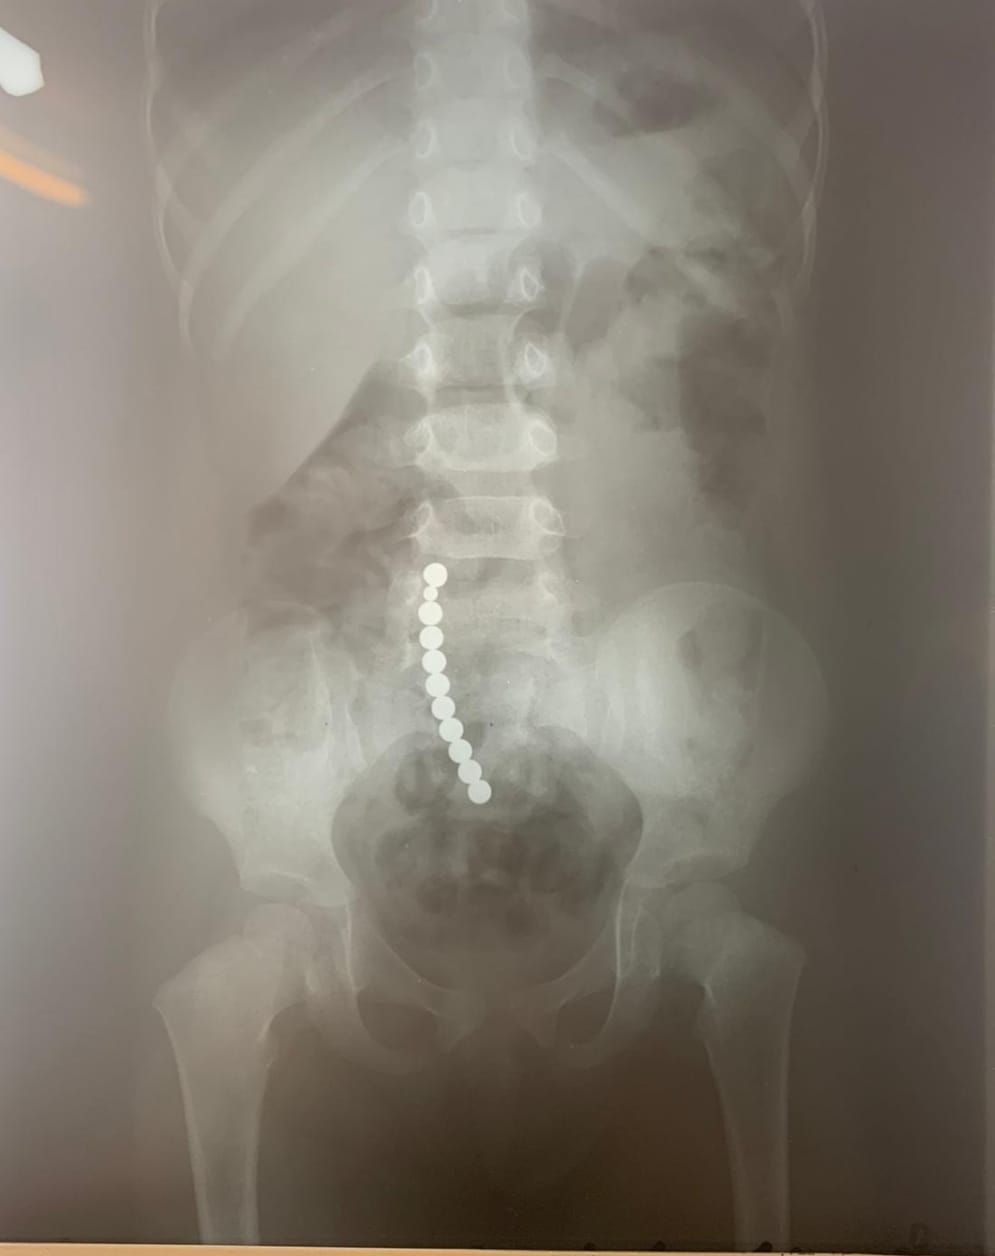

Dr. Adriana Constantineanu, medic specialist în chirurgie pediatrică atrage atenția asupra pericolului din spatele jucăriilor cu magnet. Acestea îi pot distra pe copii și pot fi fascinați de multitudinea de culori vii care îi duce cu gândul pe cei mici la bomboane, înghițindu-le.

Acești magneți sunt foarte puternici, iar ingestia lor poate duce la probleme gastrointestinale grave. Odată înghițiți sunt atrași unul spre altul chiar dacă se găsesc în secțiuni diferite ale tubului digestiv. O ansă intestinală prinsă între acești magneți se poate perfora ducând la tratament chirurgical de urgență. În secția noastră, de la începutul anului s-au prezentat trei cazuri, două fete și un băiat, cu vârste cuprinse între 2 și 4 ani. Aceștia au suferit perforații la nivelul intestinului subțire și au necesitat intervenții pentru îndepartarea porțiunii de intestin afectate”, a precizat dr. Adriana Constantineanu.